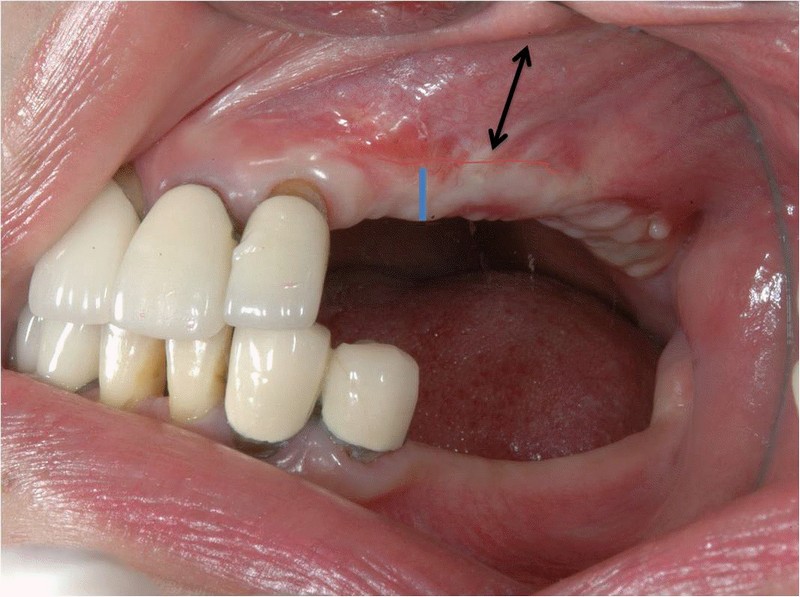

All on 4 / All on X